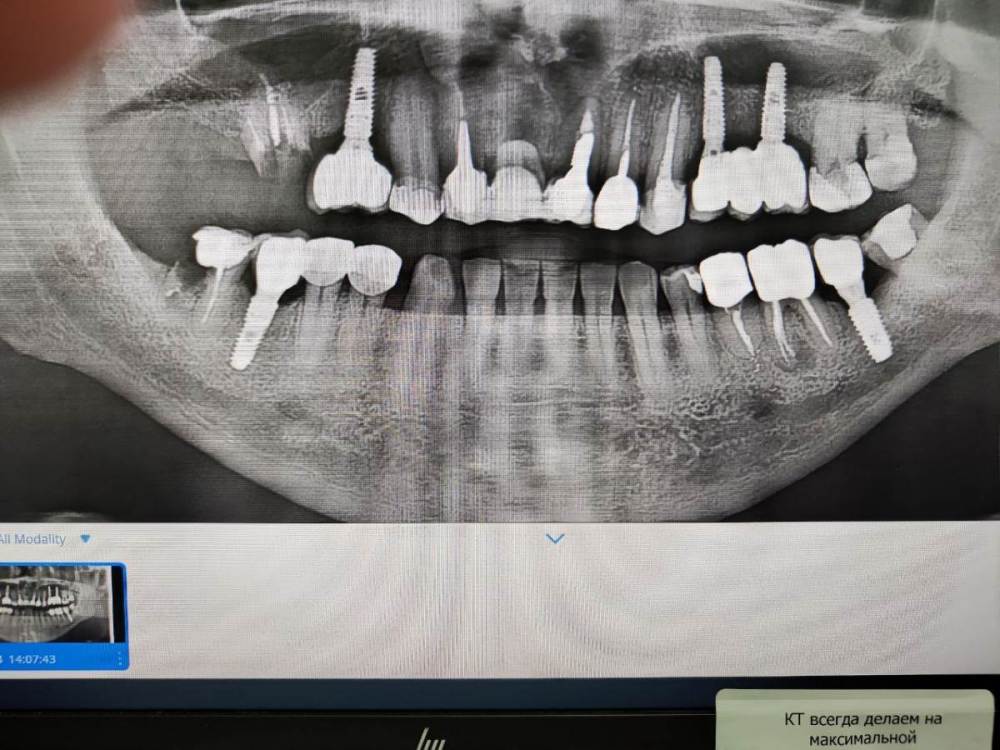

3. По поводу результатов проведенной имплантации 7 лет назад.  Один хирург  который смотрел мой снимок недавно выразил мнение, что импланты на верних челюстях выбраны избыточной длины и можно было просто поставить импланты большего диаметра и короче. Он увидел признаки резорбции кости.  Хотел бы услышать ваше мнение об этом и на сколько прав он в своих суждениях. Сколько лет еще могут простоять установленные импланты ? Про врачебную этику и пациентов знаю, но мы не раскрываем имя доктора, а если не хотите писать открыто можно написать мне в личку.  Для меня это очень важно. К доктору я естественно без претензий, но на выбор для новых операции безусловно повлияет.  Спасибо большое за то, что вы  прочитали и ваше мнение!

Компьютерная томография: https://cloud.mail.ru/public/nnZJ/N2pid2KKF

photo_2023-07-24_17-02-59.jpg

1 зуб 1.6 надо удалять, чем раньше - тем лучше, синус лифт не та операция, которую надо избегать любой ценой

2 учитывая ту картину, которую видно на панорамной реконструкции, зуб 4.7 нужно удалять

3. Высказывания консультанта остаются на его совести. На мой взгляд, особо придраться не к чему. Хотя, "докопаться" и до столба можно.

Искать нового хирурга? Решать вам.